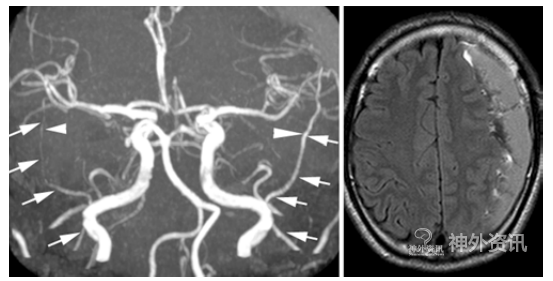

55例CSDH患者中,24例双侧半球CSDH,31例单侧半球CSDH。总共79侧CSDH的MMA直径为1.48±0.48mm,31侧无CSDH的MMA直径为0.93±0.21mm,出血侧MMA直径明显大于未出血侧(p<0.0001)(图1)。血肿大小与MMA直径无明显关系。24例双侧CSDH的患者中,血肿较大侧的MMA直径为1.48±0.52 mm,另一侧为1.46±0.59mm,两者无差异。13例患者具有CSDH发病前的头颅MRA资料,其中5例患者出现双侧CSDH,8例出现单侧CSDH。对比发病前与发病后出血侧MRA图像发现,发病前出血侧MMA平均直径为0.92± 0.23mm,发病后MMA直径为1.37±0.35mm,两者间有明显差异(图2)。而发病前和发病后未出血侧的MMA直径无明显变化(0.89± 0.16mm比0.85±0.21mm,p=0.7334)。55例对照组MMA直径明显小于CSDH组(1.05± 0.25mm比1.32±0.49mm,p<0.0001)。同时,分析结果显示,MMA直径1.3mm是预测CSDH的一个临界值,其敏感性为74.7%,特异性83.7%,约登指数0.5837,AUC值0.82817。

图1. 左. 箭头所指左侧MMA直径明显大于右侧;右. FLAIR序列显示左侧半球CSDH。